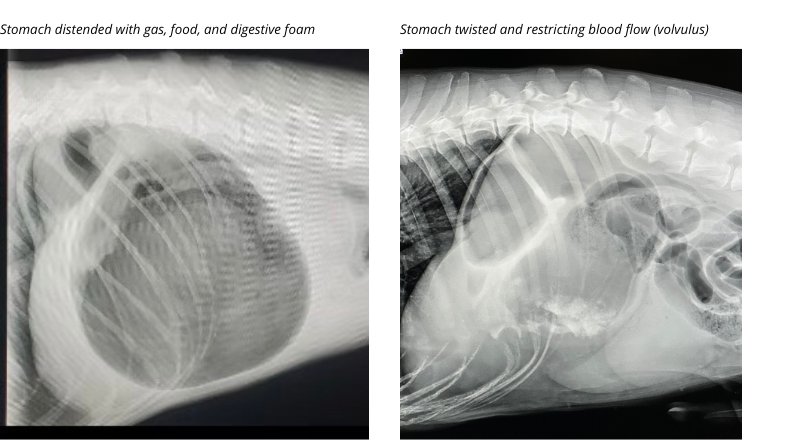

Gastric dilatation and volvulusGDV often occurs after ingesting a large meal. The accumulation of gas, food, and foam result in distention (expansion) of the stomach. In some instances, the enlarged fluid-filled stomach will flip or twist on itself. The building gas continues to expand the stomach, which if not released will cause immense pain, increased heart rate, and decreased blood flow to the surrounding tissues. Without emergency intervention, all dogs will sadly succumb to shock and organ failure. Even with advanced and prompt surgical intervention, nearly half of dogs with GDV will die due to complications.